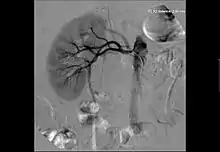

Las técnicas de diagnóstico por imagen utilizadas preferentemente son la ecografía doppler, la tomografía computerizada y la resonancia magnética. La Arteriografía por Sustracción Digital (ASD) es la exploración diagnóstica que confirma la estenosis o obstrucción, y es el paso previo al tratamiento endovascular percutáneo.